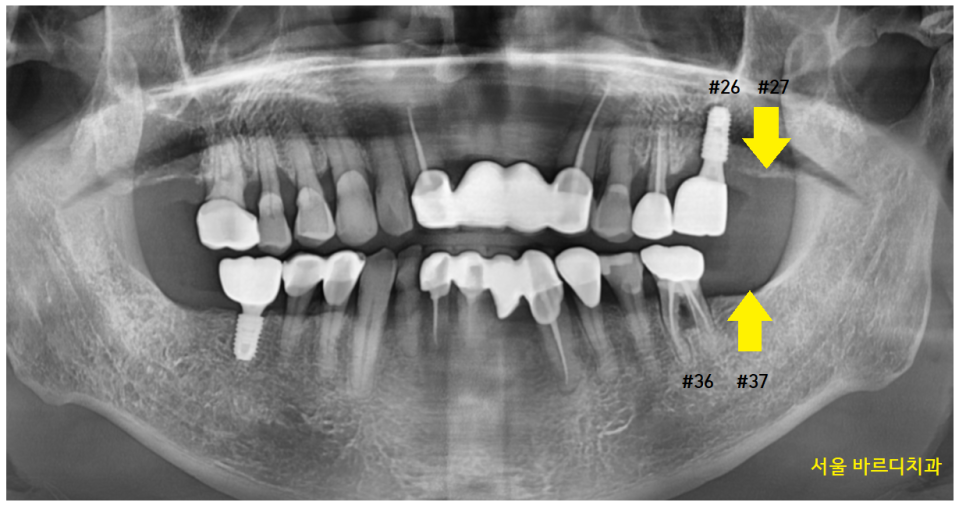

암사동 치과 환자분 사진을 함께 보실까요~?

- 윗니 맨 치아가 빠지고

아래 맨 끝 어금니가 물린다.

치아 개수가 하나가 비죠~?

오른쪽 맨 위 치아가 빠진 환자분입니다.

#17 맨 끝 어금니가 한 개가 없네요.

이 경우에는 교합을 확인합니다.

23.03.12

#47 오른쪽 아래 맨 끝에 치아가

#16 오른쪽 제 1큰 어금니와 물리네요.

#17 맨 뒤에 치아가 없지만

물리기 때문에

이 경우는 임플란트를 안 해도 됩니다.

반대의 경우를 볼까요?

아래 맨 끝 어금니가 안 물린다.

23.11.04

#27 맨 끝에 치아가 부러졌네요~

발치가 필요합니다.

구강 내 사진에서도 이가 한 개가 없죠~?

교합되는 사진을 보겠습니다.

#27 왼쪽 맨 끝 치아가 상실

#47 왼쪽 아래 맨 끝 치아가 물리는 게 없네요~

이럴 경우 맞닿은 치아가 없어서

아래 치아가 위로 쑥쑥 올라오게 됩니다.

자연치아의 손상을 방지하기 위해서라도

임플란트가 필요합니다.

24.02.22

아래 어금니를 지키기 위해서

발치 후 암사동 치과에서 임플란트를 식립하셨습니다.

#27,37 위아래로 치아가 없는 경우에는

양쪽으로 물리는 게 없어서

환자분 결정에 맡깁니다.

23.12.28

#36 왼쪽 아래 맞물리는 #26 왼쪽 위에 치아만

심는 것으로 치료를 종결